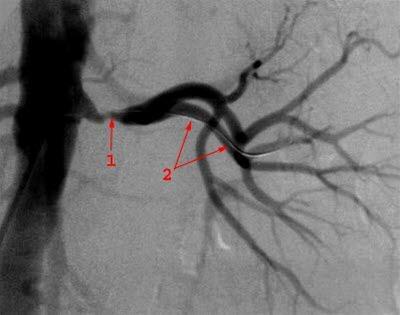

Sekundær hypertensjon betyr høyt blodtrykk forårsaket av annen sykdom. Spesielt nyresykdommer med sviktende nyrefunksjon har en tendens til å øke blodtrykket. Innsnevring av pulsåren til en eller begge nyrer (nyrearteriestenose) er en annen kjent årsak (se bildet). Enkelte sykdommer i binyrene, i bukspyttkjertelen eller hovedpulsåren, kan også forårsake høyt blodtrykk. Det samme gjelder bruk av en del medisiner, for eksempel p-piller, NSAIDs, og kortikosteroider.